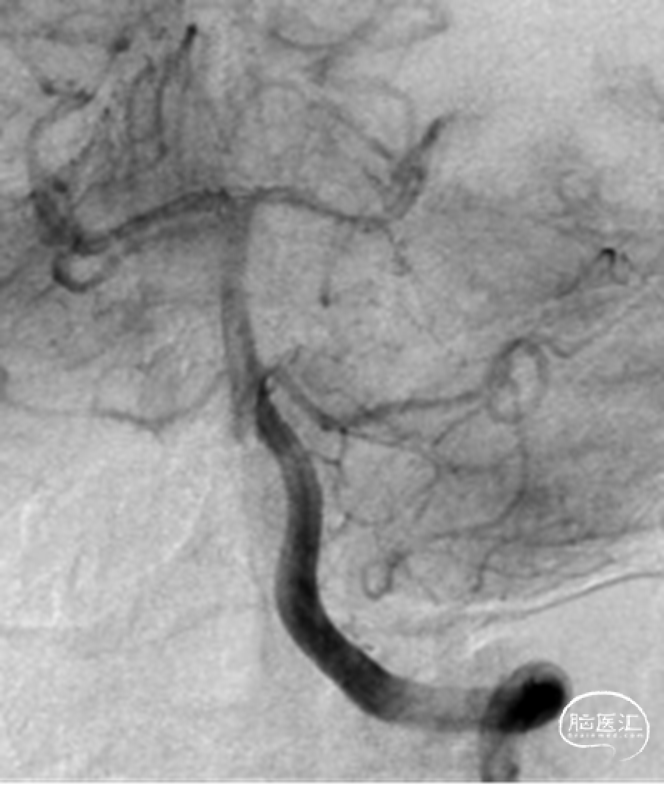

1、术后即刻和术后一年临床随访:mRS 0。

2、影像学随访:一年后的随访影像显示动脉瘤完全不显影。

一年后的随访影像